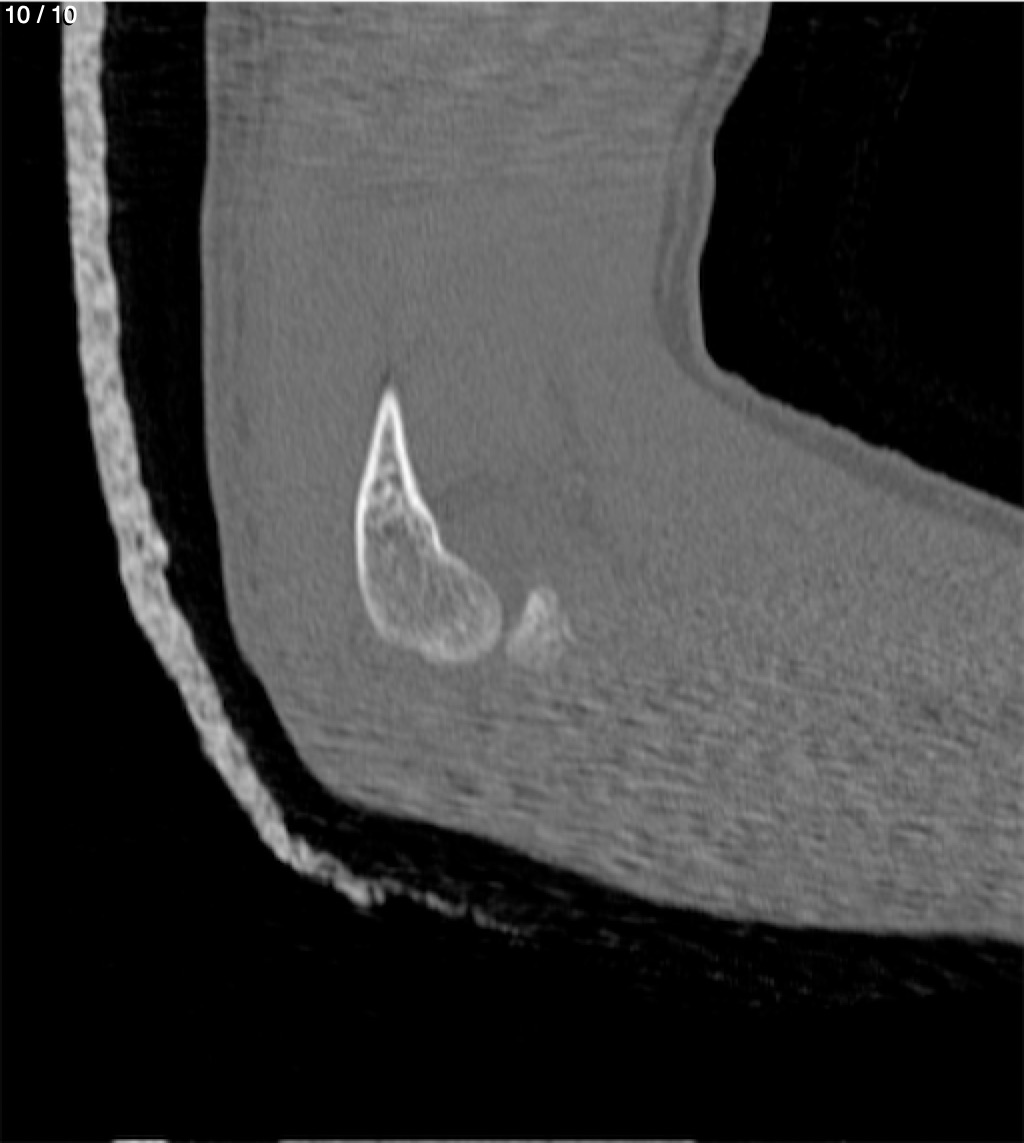

Antonio Dominguez Tino 21 A - Tac Codo Izq